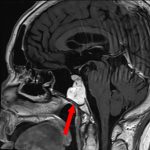

断層撮影

手術前1